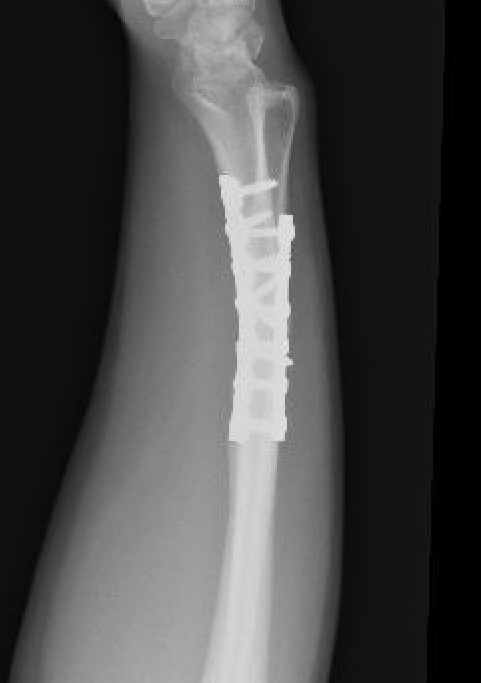

Galeazzi fracture

Galeazzi fracture with DRUJ disruption

Incidence of DRUJ instability after radius ORIF

Rettig et al J Hand Surg Am 2001

- 40 patients with Galeazzi fracture dislocations

- DRUJ instability after radius ORIF

- Type 1: radius fracture < 7.5 cm to articular surface: 55% DRUJ instability

- TYpe II: radius fracture > 7.5 cm to articular surface: 6% DRUJ instability